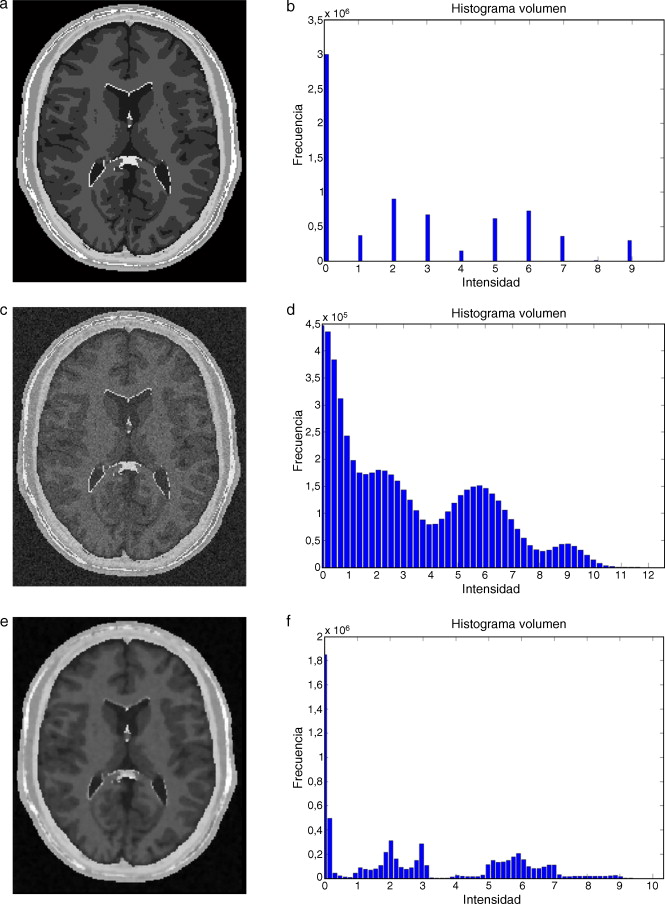

En este trabajo, se implementó una rutina de suavizado de ruido con preservación de bordes empleando la librería de difusión anisotrópica: itk::GradientAnisotropicDiffusionImageFilte r [20] . En la figura 6 se presentan los resultados obtenidos al aplicar los filtros en un phantom de IRM [15] que simulan IRM del cerebro a través de volúmenes «fuzzy» . Esta imagen de phantom tiene dimensiones de 181 × 217 × 181 (X × Y × Z ), con voxels isotrópicos de 1,0 mm3 . Por visualización se presenta el corte axial 98, sin embargo, los filtros e histogramas mostrados fueron aplicados sobre el volumen completo. En las figuras 6.a y b se presenta el corte axial 98 del phantom y el histograma del phantom completo, respectivamente. En las figuras 6.c y 6.d se presenta el corte axial 98 con ruido gaussiano aditivo y el histograma de este nuevo volumen con ruido, respectivamente. En la figura 6 .e se presenta la imagen resultante luego de aplicar al volumen de la figura 6 .e el filtro de difusión anisotrópica itk::GradientAnisotropicDiffusionImageFilte r. En la figura 6 .f es mostrado el histograma de esta imagen filtrada.

|

|

|

Figura 6. Aplicación de filtros en imagen phantom de IRM corrompida con ruido gaussiano. (a). Imagen de phantom original, vista del corte 98. (b) Histograma de (a). (c) Imagen (a) corrompido con ruido gaussiano . (d) Histograma de (c). (e) Imagen (a) suavizada con filtro de difusion anisotrópica. (f) Histograma de (e). |